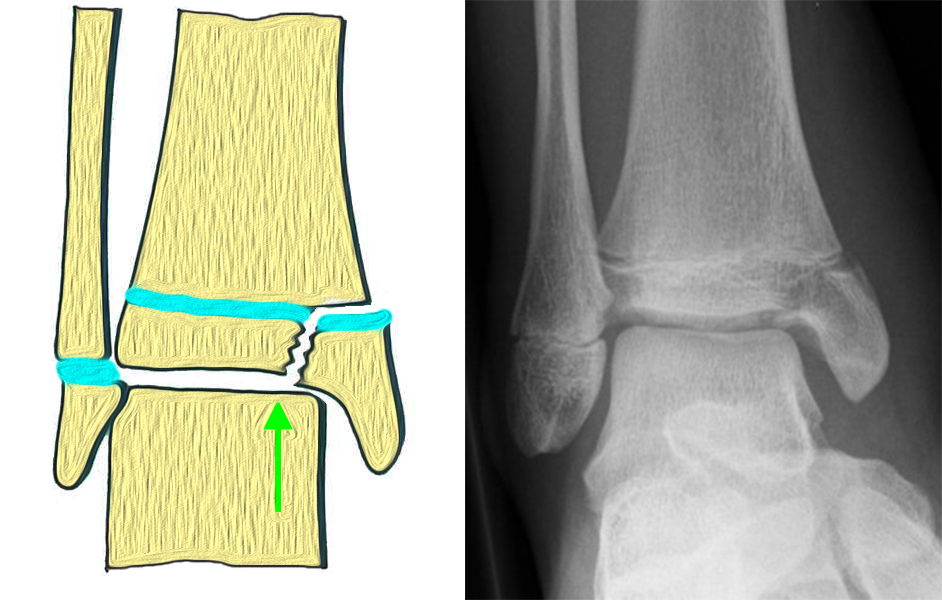

Fugengelenkfrakturen können die Wachstumsfuge durchkreuzen (Abbildung 16a), ohne oder nur mit minimaler Beteiligung der Fuge sehr weit medial liegen (Abbildung 16b) oder durch die Fuge auslaufen (Abbildung 16c). Relevant für die Wachstumsprognose ist weniger die Form der Fraktur, sondern das Alter des Patienten zum Zeitpunkt des Traumas sowie das Ausmaß der Schädigung der Wachstumsfuge, wobei eine Korrelation mit dem Ausmaß der Dislokation besteht.

Bei kindlichen Verletzungen des medialen Malleolus handelt es sich nach L. v. Laer um eine sogenannte Kadiläsion, d.h. eine Verletzung mit hohem Risiko eines schlechten Behandlungsergebnisses bei nicht korrekter Behandlung. Selbst bei optimaler Therapie ist das Risiko für spätere Wachstumsstörungen hoch, sodass diese Verletzungen nicht selten ein juristisches Nachspiel haben. Durch die Verletzung der wachstumsaktiven Zone kann es zu einem vorzeitigen Verschluss der Wachstumsfuge kommen, mit entsprechendem Fehlwachstum. Das Risiko eines vorzeitigen Verschlusses der Wachstumsfuge korreliert mit dem Ausmaß der Schädigung der wachstumsaktiven Zone. Ab dem 13. Lebensjahr wird das Risiko bei reduzierter Wachstumsaktivität zunehmend geringer.

Bei den medialen Malleolarfrakturen handelt es sich um Fugengelenkfrakturen bzw. Aitken II und III Verletzungen. Kennzeichnend ist, dass der Frakturverlauf die wachstumsaktive Zone zur Epiphyse hin durchkreuzt. Die Verletzung der wachstumsaktiven Zone macht diese Verletzungen besonders problematisch.